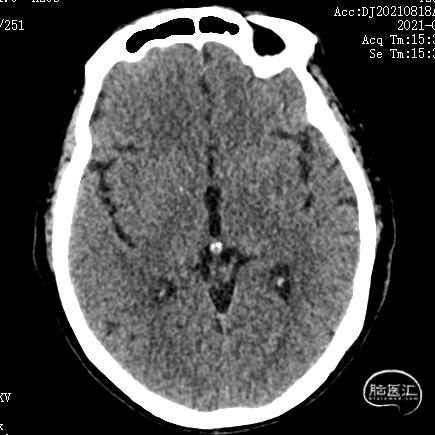

术后3天复查CT示:

1. 双侧基底节区腔隙性脑梗死;

2. 老年性脑改变;

3. 左侧颞叶致密影,考虑术后,请结合临床病史。未见大脑前载瘤动脉远端存在缺血。